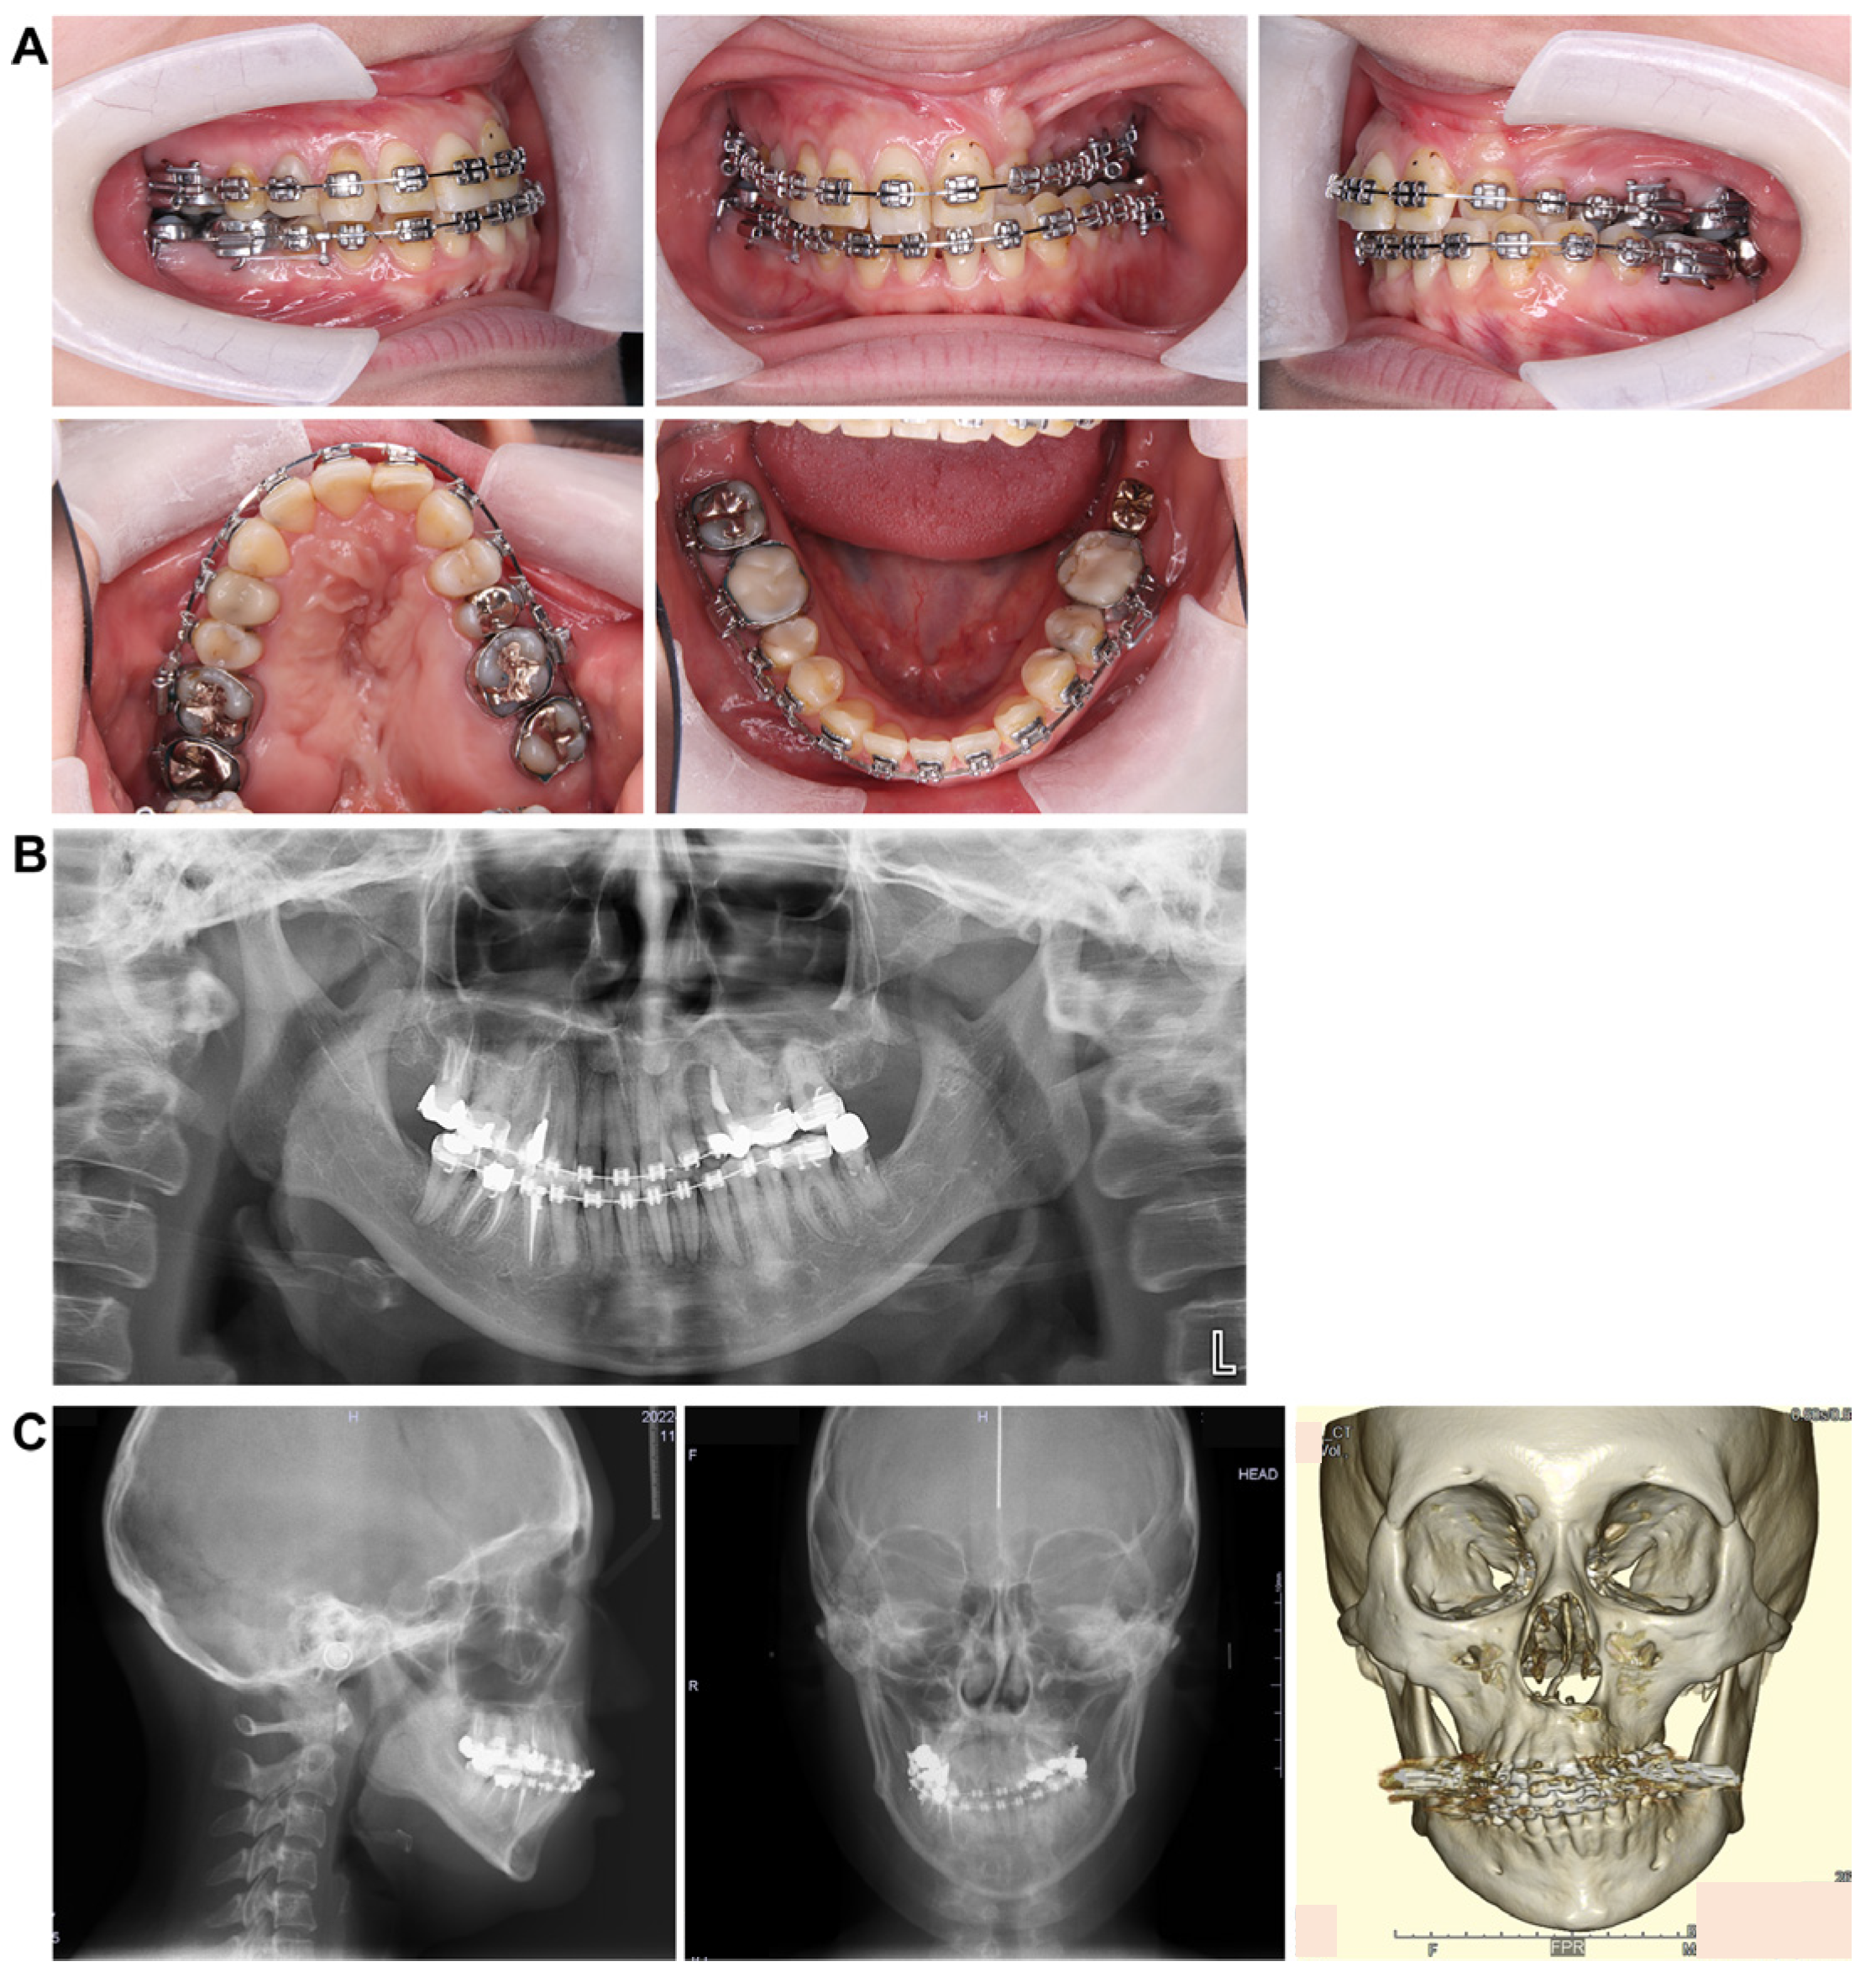

Treatment progress: During preoperative orthodontic treatment, owing to the significant asymmetry in the left and right maxillary dental arches, leveling was initiated using a sectional arch, dividing the maxilla into two segments: from the right second molar to the left central incisor and from the left canine to the left second molar. The mandibular right lateral incisor, which exhibited lingual displacement, was extracted, and a multi-bracket device (0.022 slot pre-adjusted appliance) was placed. After leveling was completed in the maxilla, the treatment transitioned to a continuous arch to minimize intraoperative movement while improving the arch width. Subsequently, to facilitate the multi-segment Le Fort I osteotomy, an open coil spring was placed between the left central incisor and the canine to gain the necessary osteotomy width. In the mandible, the extraction space from the right lateral incisor was used to improve crowding and space closure was performed (Figure 5). Dental photographs taken just before surgery confirmed that a 3.0 mm space was achieved for the surgical procedures necessary for the multi-segment approach, at which point the arch was switched to a sectional arch (Figure 6). After 15 months of treatment, preoperative orthodontics were nearly completed, and preoperative records were obtained. Crowding in the mandible was resolved, and the arch of the maxilla approached an ovoid shape with approximately 4.0 mm of expansion in width; however, the occlusion on the right side remained a crossbite (Figure 7). During orthognathic surgery, a rolling movement of 6.0° to the right was performed around the left first molar to correct the left-sided cant of the occlusal plane. A 5.0° posterior impaction centered on the anterior nasal spine and a 2.0 mm parallel shift to the left were also performed to improve the deformity and align the midline. Furthermore, a multi-segment Le Fort I osteotomy was performed to expand the maxilla by 5.0 mm from the left canine to the second molar, correcting the maxillary and mandibular arch asymmetry. During this process, a releasing incision was made at the palatal scar site, using a chisel and mallet for osteotomy.

Figure 7.

Preoperative intraoral photograph and radiographs and CT. (A) Intraoral photographs. (B) Panoramic radiograph. (C) Cephalograms and CT.

In the mandible, SSRO was performed, involving an 8.0° right rolling movement and a 2.0 mm parallel movement to the left to correct the deviation. In addition, to address the protrusion of the lower lip, a setback of 4.0 mm was performed to enhance the facial profile. Postoperatively, surgical splinting and intermaxillary fixation were performed. For bone fixation of the maxilla and mandible, titanium plates were used, with horizontal plate fixation implemented in the maxilla to improve the bone width (Figure 8). Notably, for 5 months postoperatively, intermaxillary elastics were used to stabilize the occlusion, and the multi-bracket system was removed 14 months post-surgery. During this period, at the patient’s request, a splint retainer was fabricated, and the brackets were removed to commence the retention phase.